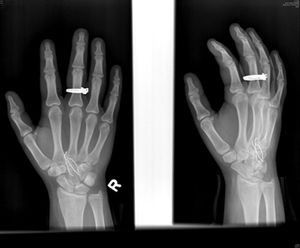

A new kind of self-mutilation is creeping into the teenage population, one that involves inserting objects into the body, according to radiologist Dr. William E. Shiels, II, who presented the first study of the adolescent phenomenon at the RSNA conference Wednesday.